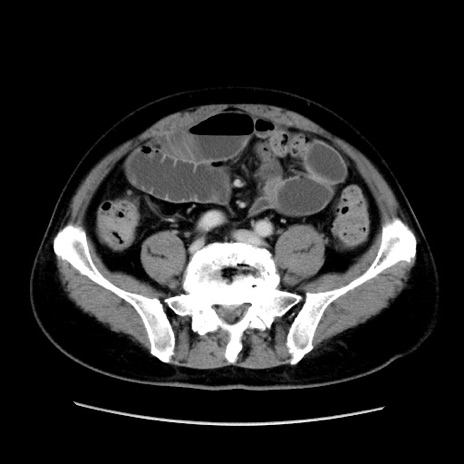

症例16(横断像)

【症例】 70歳代男性

【主訴】 腹痛、嘔吐

【現病歴】 約1ヶ月前より間欠的に腹痛と嘔吐あり、当院消化器内科を受診したところCTで多発する肝臓のLDAを指摘され、精査中であった。以降は消化器症状は安定していたが、2日前より嘔気と腹痛があり、同日より排便・排ガスが消失した。改善認めず、 本日、救急外来を受診した。

【身体所見】意識清明・会話良好、BT 36.3℃、BP 127/80mmHg、 P 80bpm、腹部:膨満あり、平坦・軟、上腹部正中および下腹部正中に圧痛あり、反跳痛なし、筋性防御なし。

【データ】WBC 7200、CRP 0.77